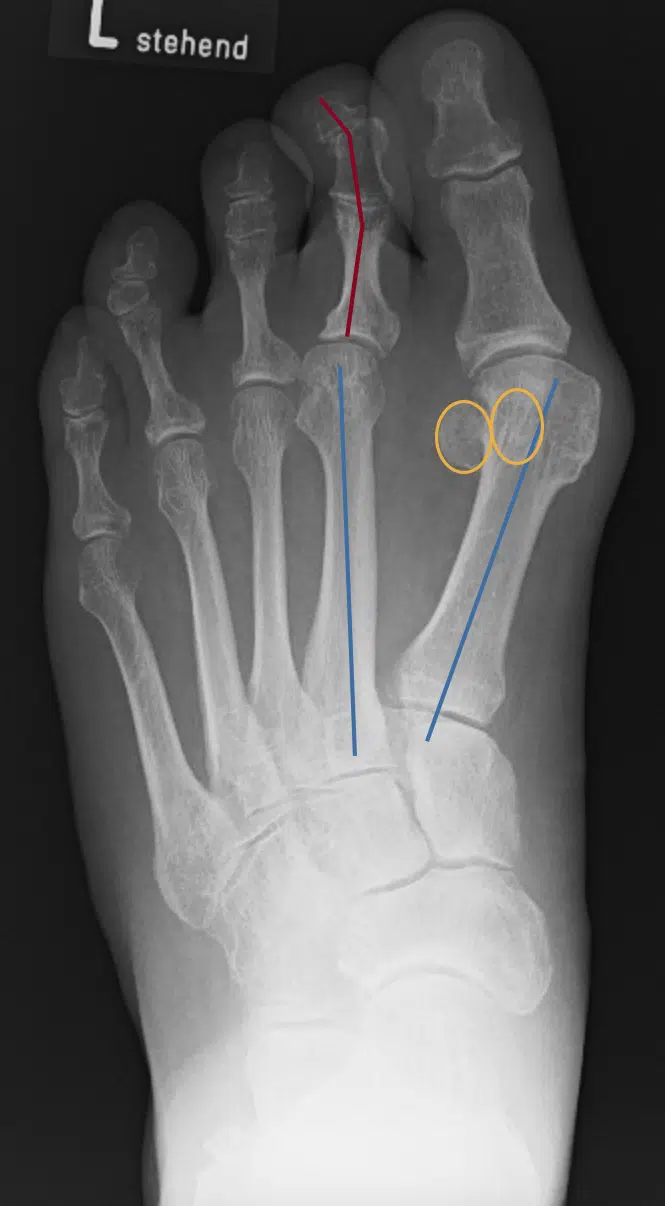

Es zeigt sich eine ausgeprägte Hallux-valgus-Fehlstellung: Die orange markierten Sesambeine sind deutlich nach lateral verlagert, die mediale Köpfchenprominenz von MT I ist betont. Die blauen Achsen kennzeichnen die Längsachsen von MT I und MT II und belegen einen pathologisch vergrößerten Intermetatarsalwinkel (IMR-1/IMA) mit Spreizung des ersten Strahls. Zusätzlich fällt am zweiten Strahl eine Z-förmige Achsabweichung (rot) von Grund- und Mittelphalanx („Zick-Zack-Zehe“) auf.